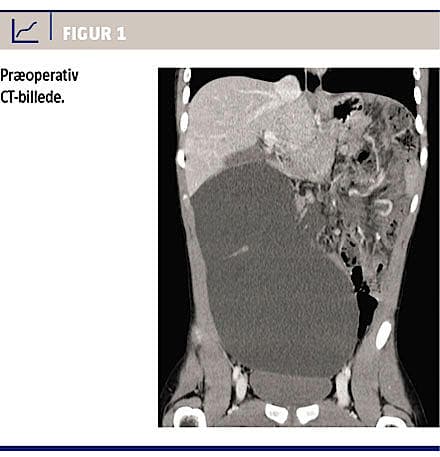

En UL-skanning suppleret med en CT (Figur 1) viste en stærkt dilateret cystisk struktur på 14 cm i diameter i højre side af abdomen, mens tarmpakettet var displaceret opadtil mod venstre, og mesenteriet tilsyneladende var torkveret 360 grader i retning mod uret. Ved akut laparotomi fandt man i tyndtarmskrøset en 25 × 15 cm stor cyste med en tyndtarmsslynge liggende fladtrykt og afklemt hen over midten (Figur 2). Cysten blev excideret in toto med samtidig resektion af det involverede tyndtarmssegment (15 cm), og den øvrige tarm blev detorkveret og genanbragt anatomisk intraabdominalt. Det postoperative forløb var ukompliceret, og drengen blev udskrevet på den tredje postoperative dag med genetableret normal tarmfunktion.